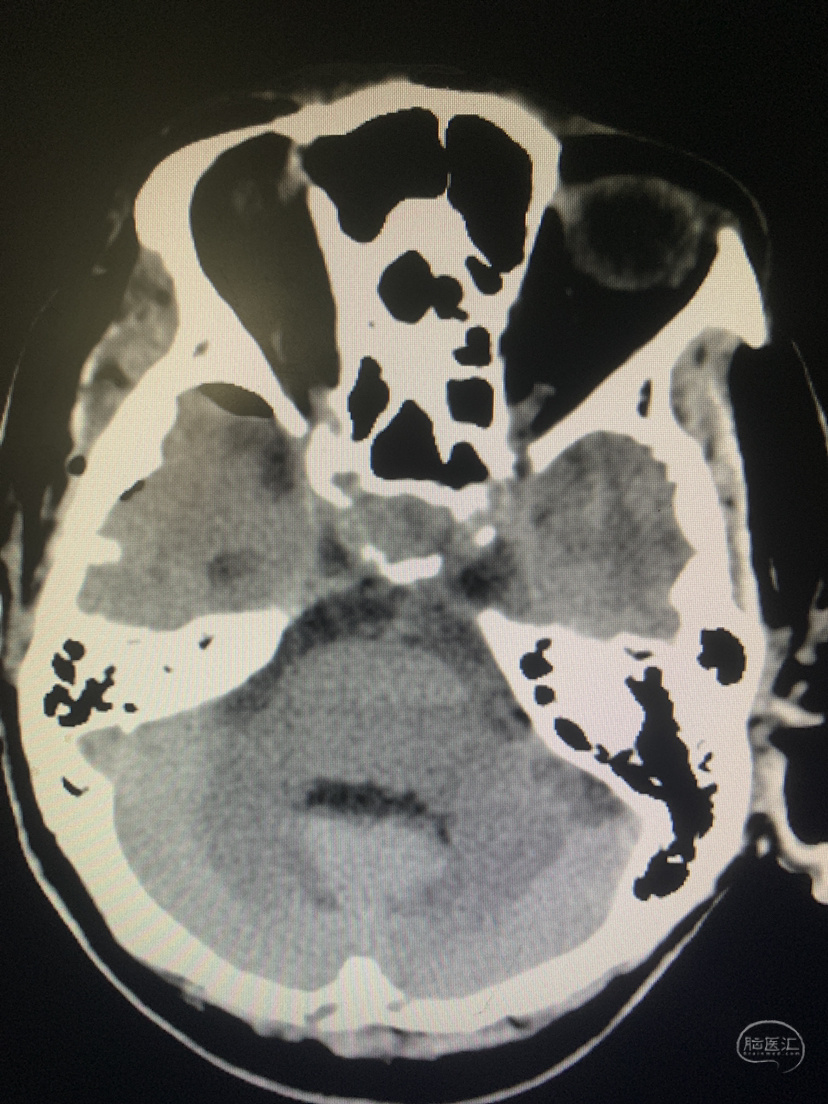

术前CT

神志昏迷双瞳散大对光反射迟钝入院,入院后甘露醇脱水加地米静滴后患者神经功能有改善,能摸索定位,瞳孔反射改善。考虑占位大直接切除可能出血多,拟术前栓塞处理,但造影发现栓塞不易风险高后放弃栓塞。

术前CT